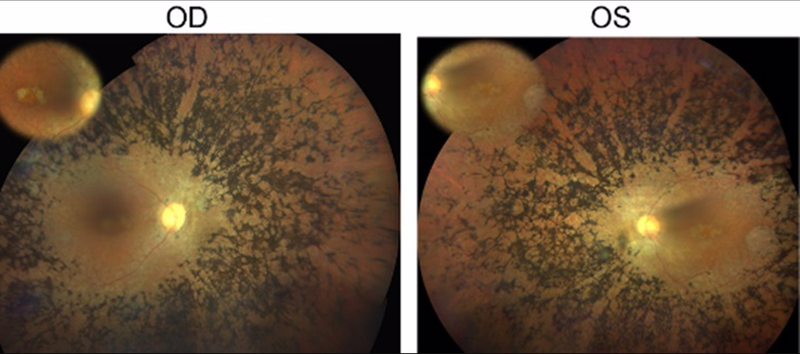

Fondo de ojo del paciente con retinitis pigmentosa en el que se ha identificado la mutación en el gen CFAP20. OD=ojo derecho, OS=ojo izquierdo. Fuente: Europa Press

Por último, la estrategia validada se ha aplicado sobre un conjunto de 14 individuos pertenecientes a familias de DHR sin causa genética conocida. Como resultado de ello se ha podido identificar una variante en el nuevo gen candidato CFAP20 que segrega con la enfermedad en una familia consanguínea de RP no sindrómica.

Los estudios de expresión (qPCR) y de localización (inmunohistoquímica) mostraron la presencia de CFAP20 en la retina humana. Aunque variantes en CFAP20 no se han asociado anteriormente con la aparición de ninguna patología en humanos, estudios previos en modelos animales y celulares han demostrado que CFAP20 tiene un papel clave en el funcionamiento y morfogénesis del cilio, apoyando su posible implicación en el desarrollo de ciliopatías humanas, como son algunos tipos de DHR. Por último, se sabe que CFAP20 interactúa con otra proteína ya asociada a la retinosis pigmentaria, ARL2BP.